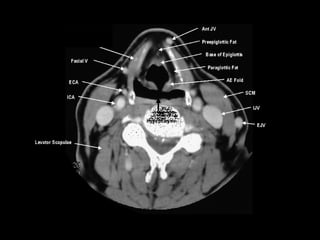

Radiographers use medical imaging equipment like X-rays and MRIs to produce images of patients' internal structures and organs. They are responsible for positioning patients, operating scanning machines, and ensuring quality images. Radiographers must have strong attention to detail, excellent communication skills, and the ability to work well under pressure to accurately capture anatomical features and diagnose any abnormalities.